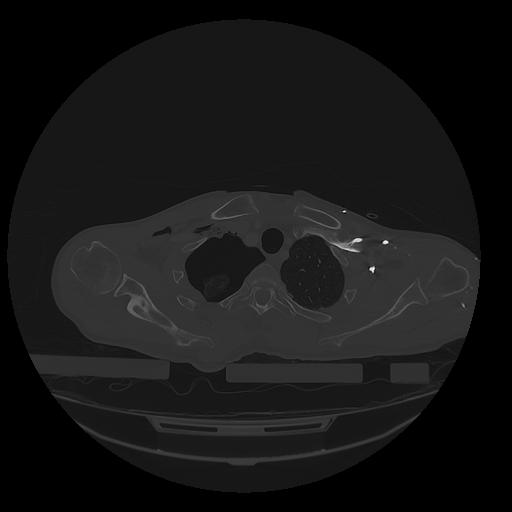

31 PULMON,CE,Vol,1.0,PULMON,,